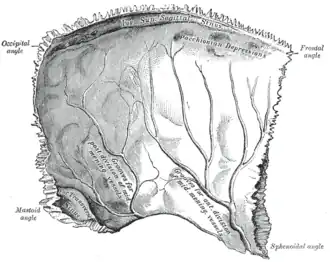

Лобная кость. Внутренняя поверхность